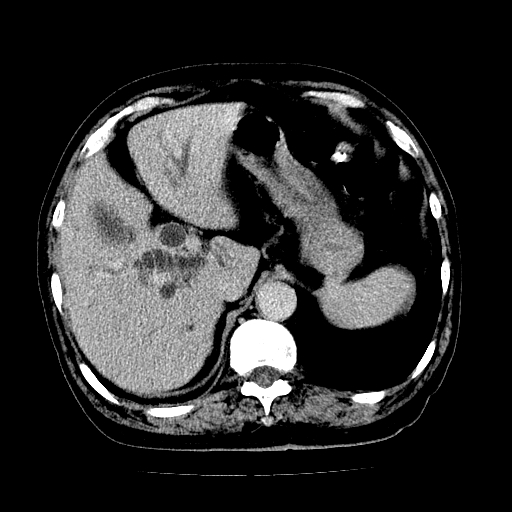

男,71岁,皮肤黄染四天。

肝内外胆管及胆总管上段扩张,考虑为梗阻所致,建议mrcp检查。

考虑胆总管癌并肝内外胆管扩张。

胆管癌并肝内外胆管扩张。

支持考虑胆总管癌并肝内外胆管扩张。 局部应薄扫。心包钙化。

胰腺上端胆总管内见软组织影,强化不明显,结合临床,还是考虑低位梗阻性黄疸,胆总管癌可能性大